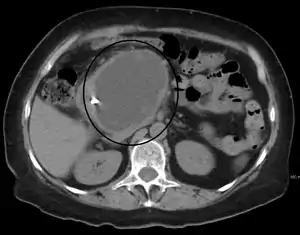

A pancreatic pseudocyst as seen on CT

CT scan

• Computerized tomography[10] – this is the gold standard for initial assessment and follow-up.